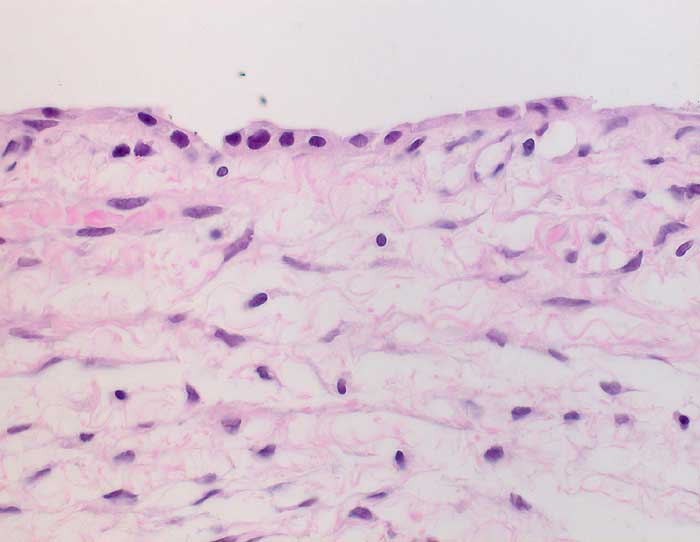

Seröses Zystadenom des Ovars

Fibrosierter Zystenbalg ausgekleidet von einem einschichtigen kubischen Epithel mit kleinen runden Kernen ohne Atypien. Der Epithelbelag fehlt stellenweise.

6cm grosse Ovarialzyste.

Histologie

400